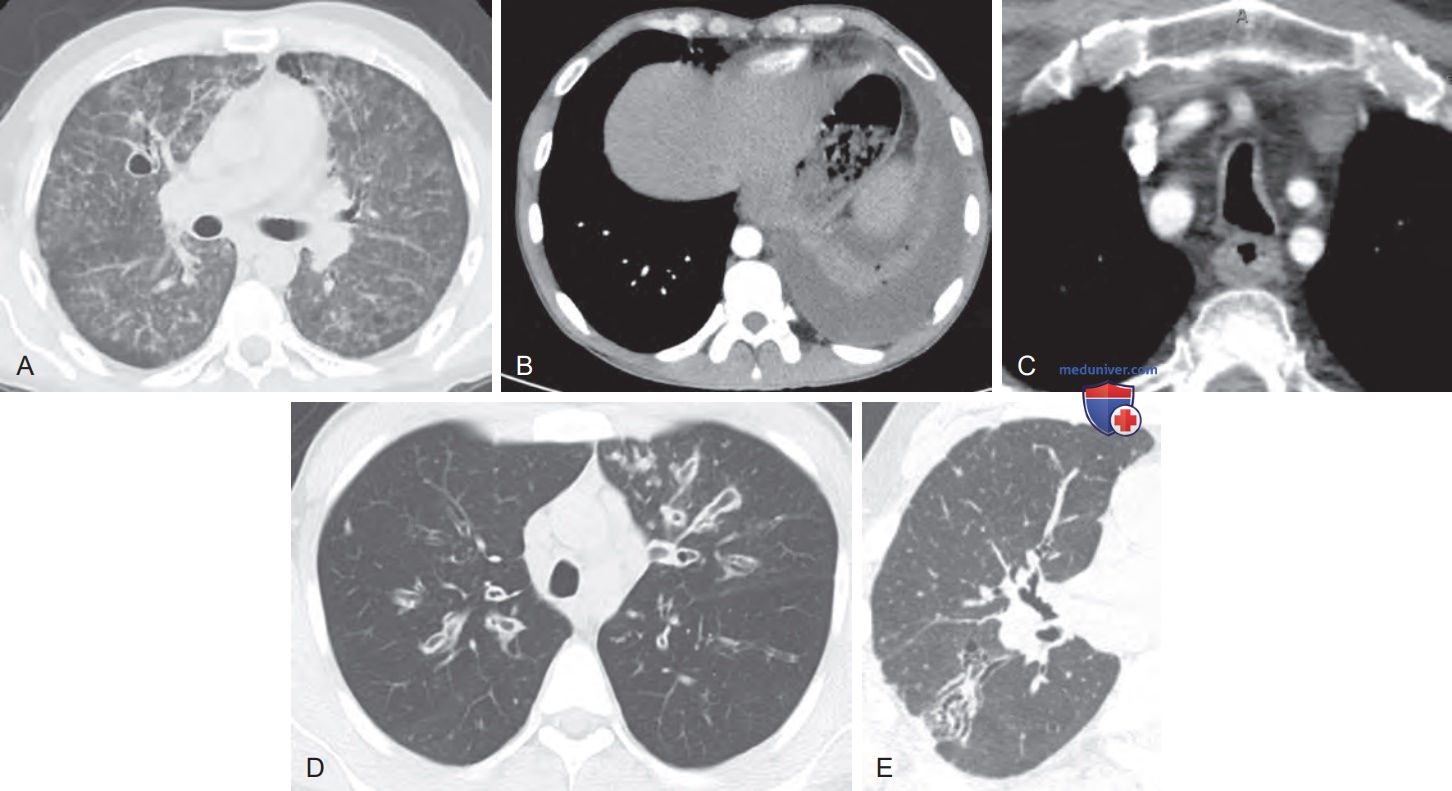

Кт признаки эмфиземы